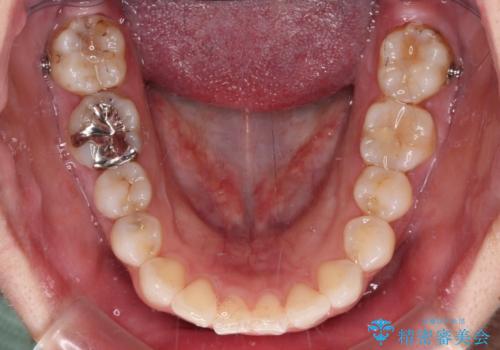

- 前歯のデコボコを治したいとのことで来院された患者様です。

上下顎ともに歯列全体の後方移動とIPR(歯と歯の間を削る)によってデコボコが解消するように設計し、インビザラインにより治療を行うこととしました。

しっかりと装着時間を守ってくださったのですが、途中妊娠にともなう悪阻や出産といったイベントがあり、予定よりも治療期間が長くなりました。